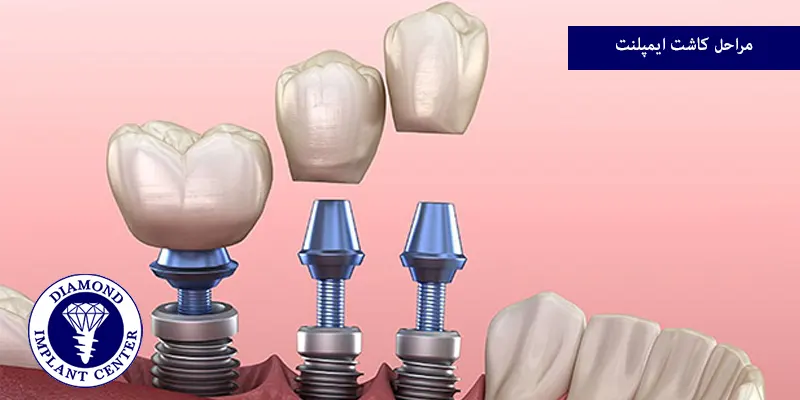

مراحل کاشت ایمپلنت

پس از انجام تمام آمادگیهای لازم، مراحل ایمپلنت دندان اجرا می شود، این بخش شامل چند مرحله کلیدی است که با دقت و مهارت توسط دندانپزشک انجام میگیرد.

جراحی کاشت پایه (فیکسچر)

این مرحله اصلیترین بخش جراحی در مراحل ایمپلنت دندان است، ابتدا بیحسی موضعی تزریق میشود تا شما هیچ دردی احساس نکنید و سپس دندانپزشک یک برش کوچک روی لثه ایجاد میکند تا به استخوان فک دسترسی پیدا کند، به کمک ابزارهای دقیق، یک حفره کوچک در استخوان ایجاد میشود.

پایه ایمپلنت که معمولا از جنس تیتانیوم و به شکل پیچ است، به آرامی درون این حفره قرار داده میشود، تیتانیوم فلزی است که بدن انسان به خوبی آن را میپذیرد و با استخوان سازگاری دارد و در نهایت، لثه بخیه زده میشود.

قرار دادن هیلینگ اباتمنت

پس از اینکه دندانپزشک از جوش خوردن کامل پایه به استخوان مطمئن شد، نوبت به مرحله بعد میرسد، در یک جراحی کوچک و ساده (معمولا فقط با بیحسی موضعی)، برشی کوچک روی لثه ایجاد میشود تا سر ایمپلنت نمایان شود و سپس یک قطعه کوچک به نام هیلینگ اباتمنت یا کلاهک التیامبخش روی ایمپلنت پیچ میشود.

نصب اباتمنت نهایی و روکش

آخرین مرحله، نصب روکش نهایی است، ابتدا هیلینگ اباتمنت برداشته میشود و یک قطعه رابط دیگر به نام اباتمنت نهایی روی پایه ایمپلنت پیچ میشود و اباتمنت نهایی به عنوان تکیهگاه روکش عمل میکند، سپس روکش ساخته شده در لابراتوار، روی اباتمنت قرار داده شده و به وسیله چسب مخصوص دندانپزشکی یا پیچ محکم میشود.

دندانپزشک تناسب روکش با دندانهای دیگر و راحتی شما هنگام جویدن را بررسی میکند و با نصب روکش، فرآیند کاشت ایمپلنت به پایان میرسد و شما میتوانید از دندان جدید خود استفاده کنید.